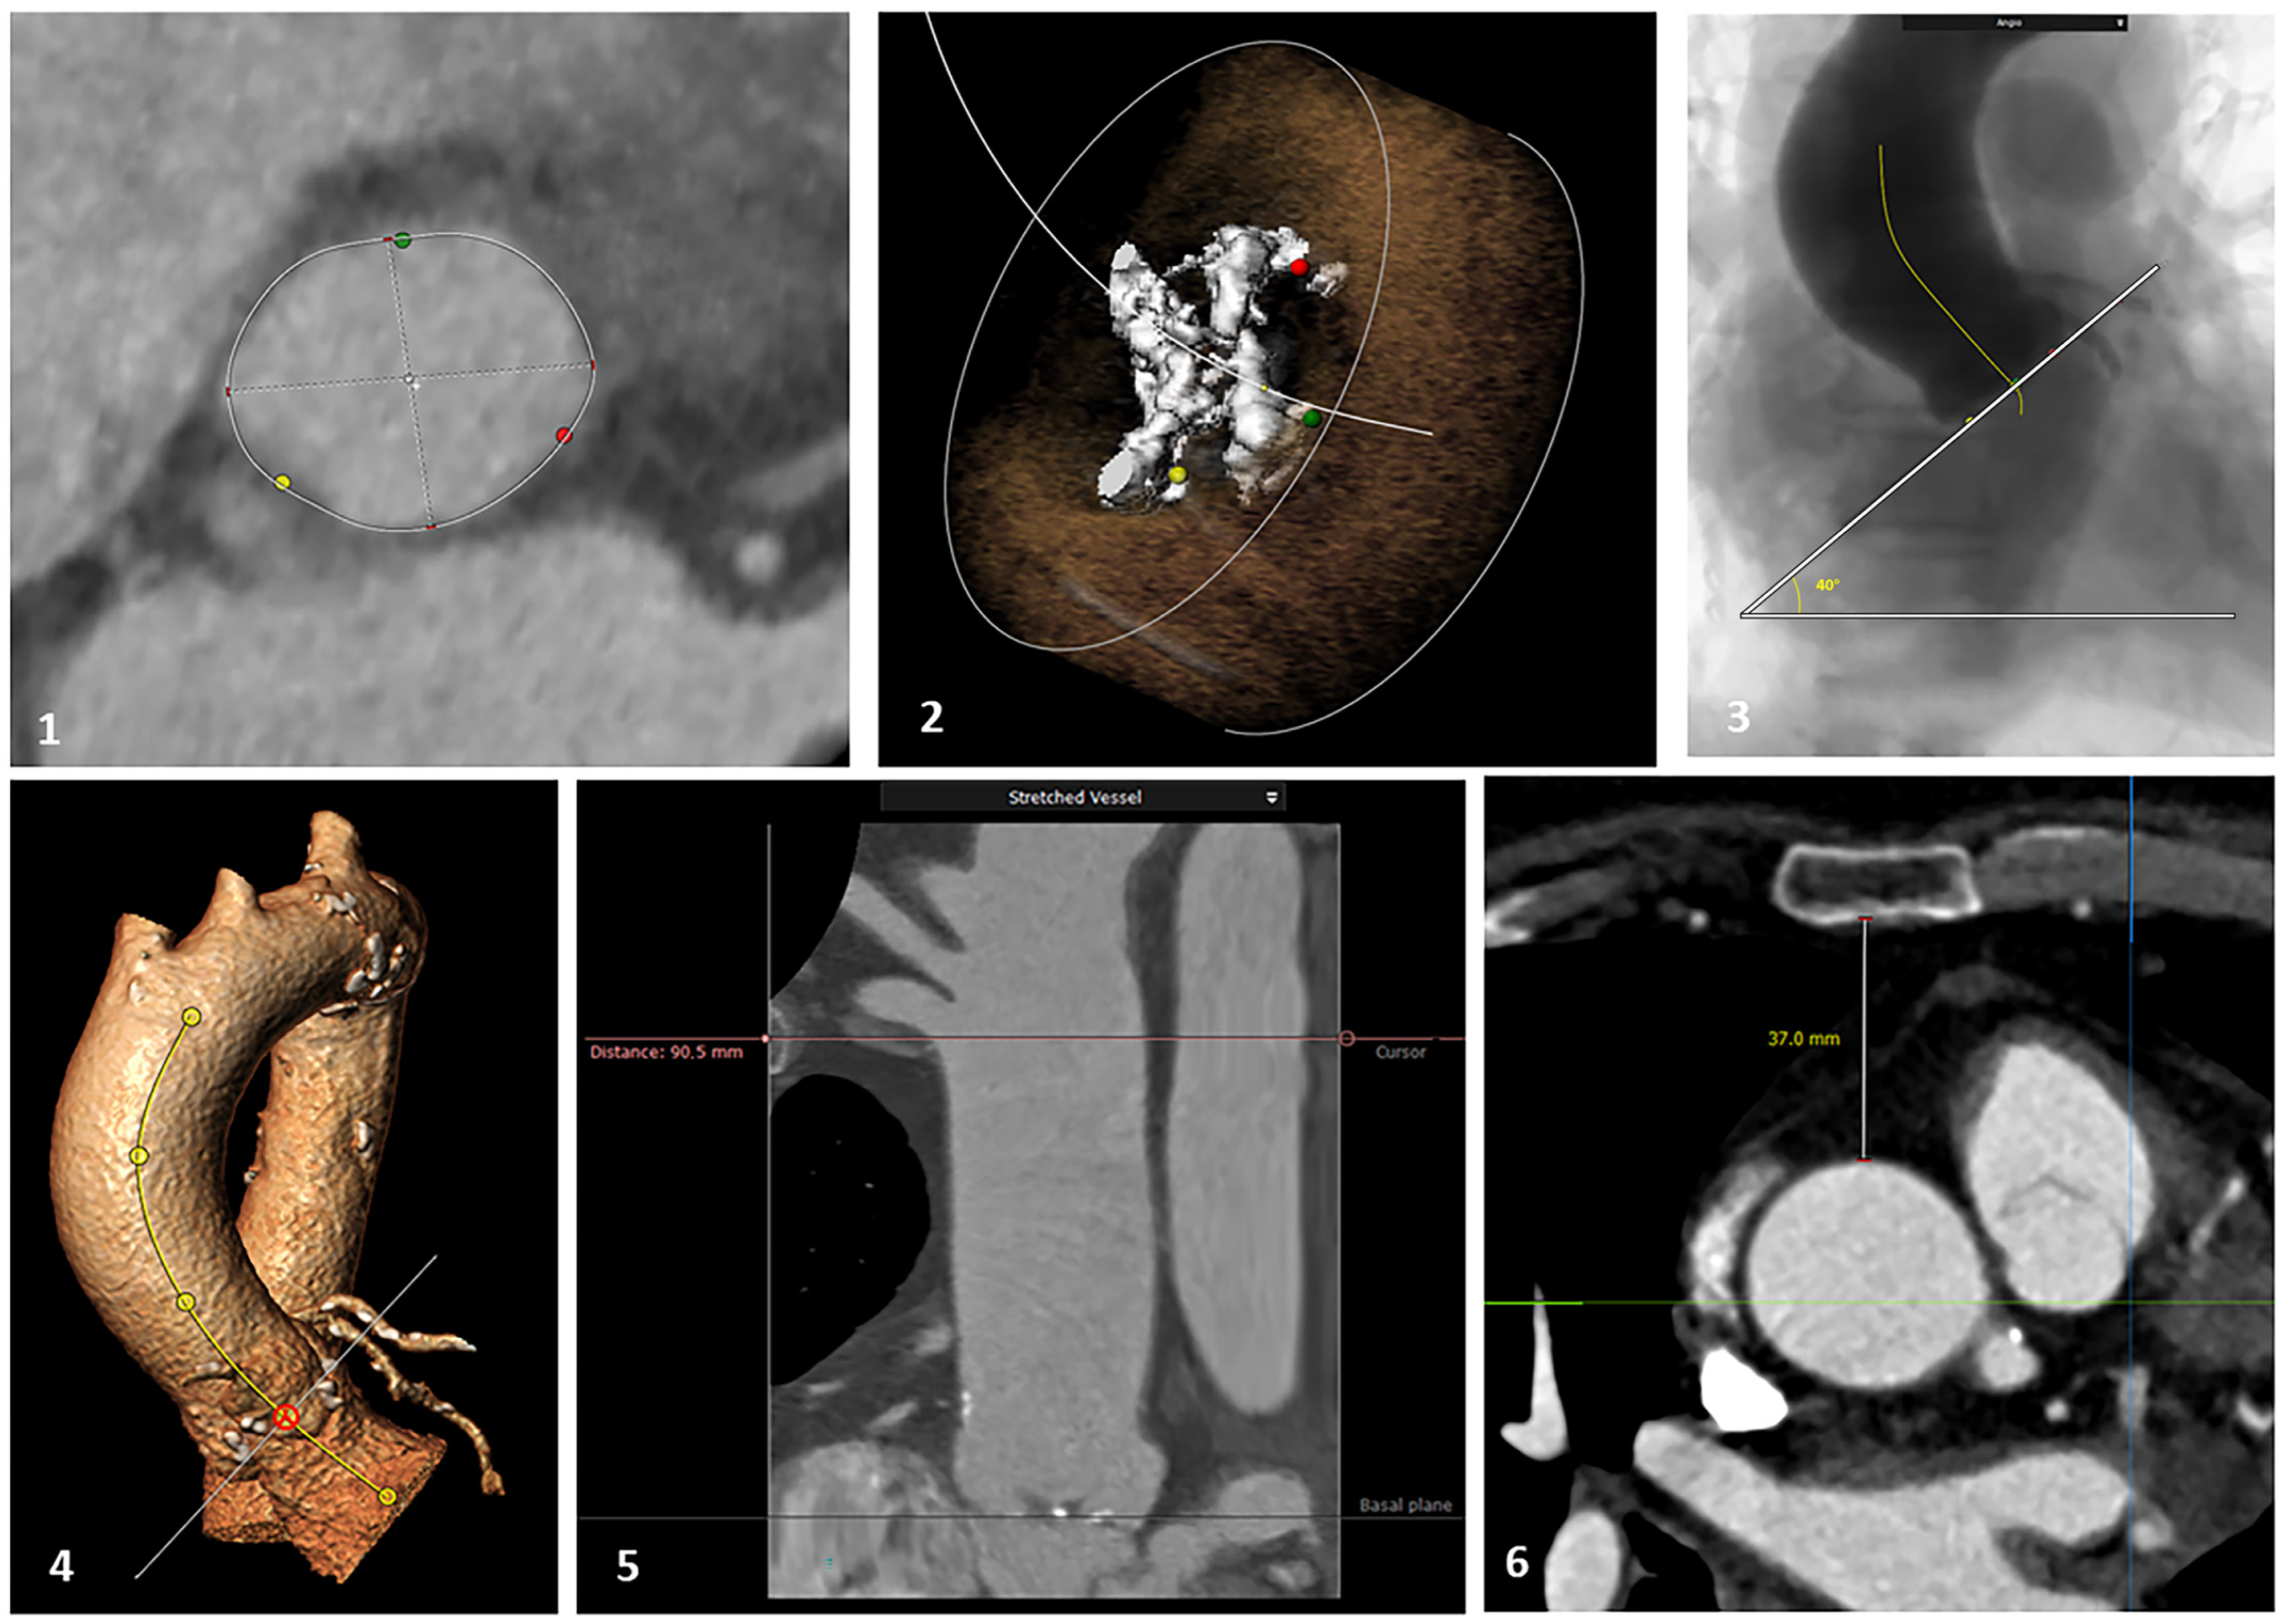

The studies were re-analysed, and the images were reconstructed with 3mensio software (v10.0, Pie Medical Imaging, Maastricht, The Netherlands). The following parameters were systematically assessed: aortic annulus dimensions (obtained in the double oblique plane after multi-planar reconstruction),aortic valve calcium score (calculated by the software), ascending aorta length from aortic annulus to the origin of the brachiocephalic trunk (measured on the reconstructed stretched vessel), inclination angle of the aortic annulus (considered to be the angle between the aortic annulus plane and the horizontal plane) and the distance between the sternum (posterior ridge) and the aorta at the level of the sino-tubular junction (Figure 2).

Figure 2. Example of the CT scan parameters assessed: (1) annular dimensions; (2) calcium score; (3 and 4) aortic annulus inclination angle; (5) ascending aorta length; (6) sternum/STJ distance.